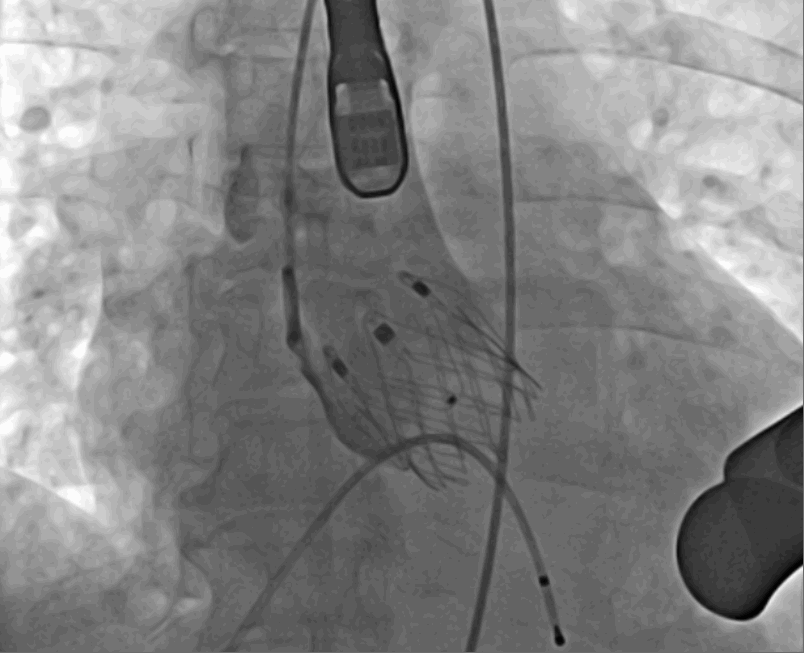

術后DSA影像

手術采用經心尖入路,對患者進行全麻后,在左側心尖處做3-4cm微創手術切口,在DSA及超聲引導下手術順利完成。從導入器械到完成瓣膜置入,僅耗時約10分鐘。術后即刻主動脈瓣返流程度由術前大量返流轉為消失,患者于導管室拔除氣管插管,次日由ICU轉入普通病房。

此次手術是Ken-Valve®經導管主動脈瓣置換系統首次在西北地區臨床應用,手術的成功標志著在該區域主動脈瓣疾病的治療手段更加的多樣化,為重度主動脈瓣返流患者提供更多的治療選擇。